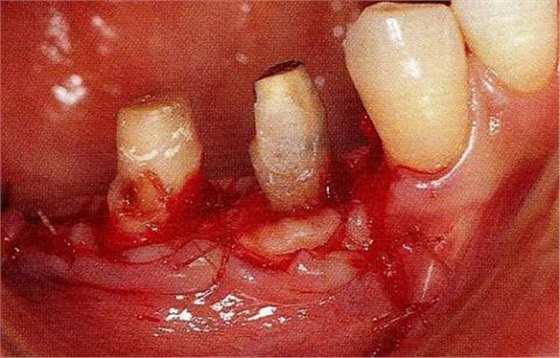

圖17-1 ( 左 ),2 ( 右 )▲右下4近中9mm的骨緣下缺損,兩側(cè)全口橋體修復(fù),但是這顆患牙保留的情況下會(huì)影響牙列的維持,鄰接牙的骨水平在較高的位置,拔牙后可以獲得平坦的骨水平。即使是右下4嘗試再生療法,假說(shuō)可以100%的成功,右下3遠(yuǎn)中骨水平也會(huì)形成3mm以上的臺(tái)階。而且再生治療也需要患者登上1年半以上的時(shí)間。所以最終選擇拔牙的處理。

圖17-3▲拔牙的同時(shí)做骨外科處理,讓殘留的骨可以盡量平坦化。為了獲得頰側(cè)的附著齦,采用了游離齦瓣的處理。